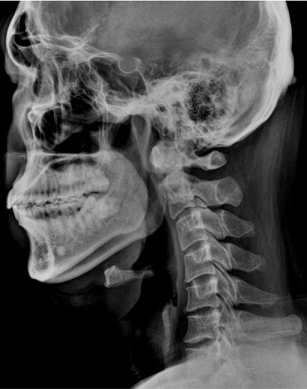

위 사진처럼 목뼈(경추)의 형태가 뒤쪽으로 나온 경우를 경추역커브(reverse C-curve)라고 하며 정상은 이와 반대인 C자 형태를 갖추고 있어야 합니다

옆모습에서 봤을 때 귀와 어깨의 가장 튀어나온 위치가 일자로 있어야 정상 목곡선이라고 할 수 있습니다

이러한 근육의 불균형은 목의 뻐근함으로 이어지며 시간이 지나면서 목의 커브가 일자형태를 지나 역 C자형을 만들게 되면서 더 큰 통증을 유발합니다